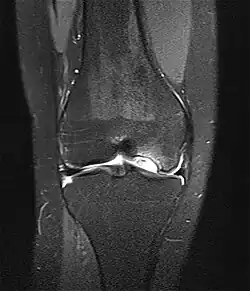

MRT-Bild einer Osteochondrosis dissecans des Kniegelenkes

MRT-Bild einer Epiphyse des Kniegelenkes. Pfeile zeigen auf die Epipysenfugen, rot für Längenwachstum, gelb für Dickenwachstum, auf der „sekundären Fuge“ um den Kern befindet sich der Gelenkknorpel, durch feinste schwarze Linie getrennt

MR-Tomographie: OD großer stabiler Herd eines 15-Jährigen

Die Erkrankung kann zufällig auf einem Röntgenbild entdeckt werden, das nach einem Unfall von der Knieregion, vom Sprunggelenk oder vom Ellbogen angefertigt wird. Bei typischen Beschwerden von aktiven Kindern und Jugendlichen kann mit einem solchen einfachen Röntgenbild die eindeutige Diagnose schon gestellt werden, weil der veränderte Knochen unterhalb der Gelenkoberfläche an typischer Stelle in der Oberschenkelrolle am Knie identifiziert werden kann. Manchmal kann eine sogenannte Tunnelaufnahme mit gebeugtem Knie die Schädigungszone noch besser zeigen. Zur genaueren Analyse sollte eine Kernspintomographie (MRT) durchgeführt werden. An den dabei erzeugten Bildern lässt sich die Lage und Größe des Befundes, die Tiefenausdehnung und vor allem eine Beteiligung des darüberliegenden Knorpels genau ausmessen. Es sind damit auch Aussagen zur Stabilität des Befundes zu treffen. Daraus ergeben sich dann entscheidende Anhaltspunkte für therapeutische Konsequenzen. Für die Verlaufsbeurteilung der Erkrankung eignet sich am besten das MRT, aber ggf. auch wieder die einfache Röntgenuntersuchung. Aufgrund der extrem hohen Kosten für das MR in den USA werden die Verläufe dort bis heute weitgehend nur mit Röntgenbildern dokumentiert, was zu eigenen Empfehlungen zur Verlaufsbeurteilungen führt. Generell wären aber die MR-Untersuchungen das Verfahren der Wahl. Sie erlauben eine differenzierte Beurteilung der unterschiedlichen Kriterien für Ausheilung, Instabilität und drohende Dissektion. Untersuchungen mit Sonographie können zuverlässige, aber nur orientierende Befunde am Femurkondylus erheben. Es ist damit zum Beispiel ein schneller, kostengünstiger und sicherer Ausschluss des Befalls auch der Gegenseite möglich.

Derselbe Patient: Großer Gelenkflächendefekt nach Dissektion des oben dargestellten OD-Herdes im Kernspinbild